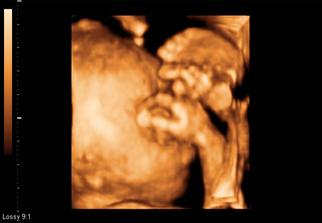

Natálka - náš maličký zázrak

krásne...je až neuveriteľné aký nádherný život v nás žije 🙂

krasne, naozaj.....mas obrocske stastie...ja som bola na 3d a 4d uz 2x a malinka si stale zakryvala ruckami tvaricku, takze mi lekar zial nic nenahral☹( este o 2 tyxzdne n poradni vyskusame a potom uz ho nebudem obtazovat....